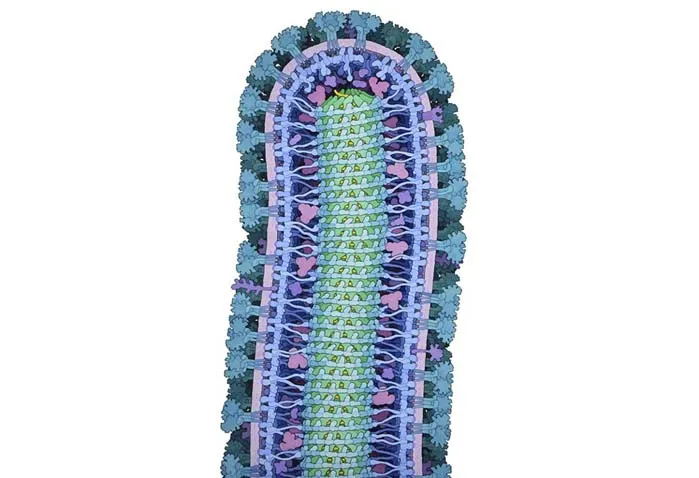

ویروس ابولا

این طراحی، ساختار درونی یک ویروس ابولا را نشان میدهد. هستهی مرکزی هم به شکل سه بعدی نشان داده شده تا ساختار درونی بیشتر مشخص باشد.

پهنای ویروس ابولا حدودا ۱۰۰ نانومتر (۰٫۰۰۰۱ میلیمتر) است؛ این یعنی تقریبا ۲۰۰ برابر کوچکتر از اکثر سلولهایی که آنها را آلوده میکند.

طراح این تصویر از رنگهای ملایم استفاده کرده تا عناصر مختلف این ویروس کوچک و مرگبار را نشان دهد. این تصویر نشان میدهد که با طراحی میتوانیم جزییات زیادی را را در سطوح مختلف با زیبایی و وضوح بالایی به تصویر بکشیم.